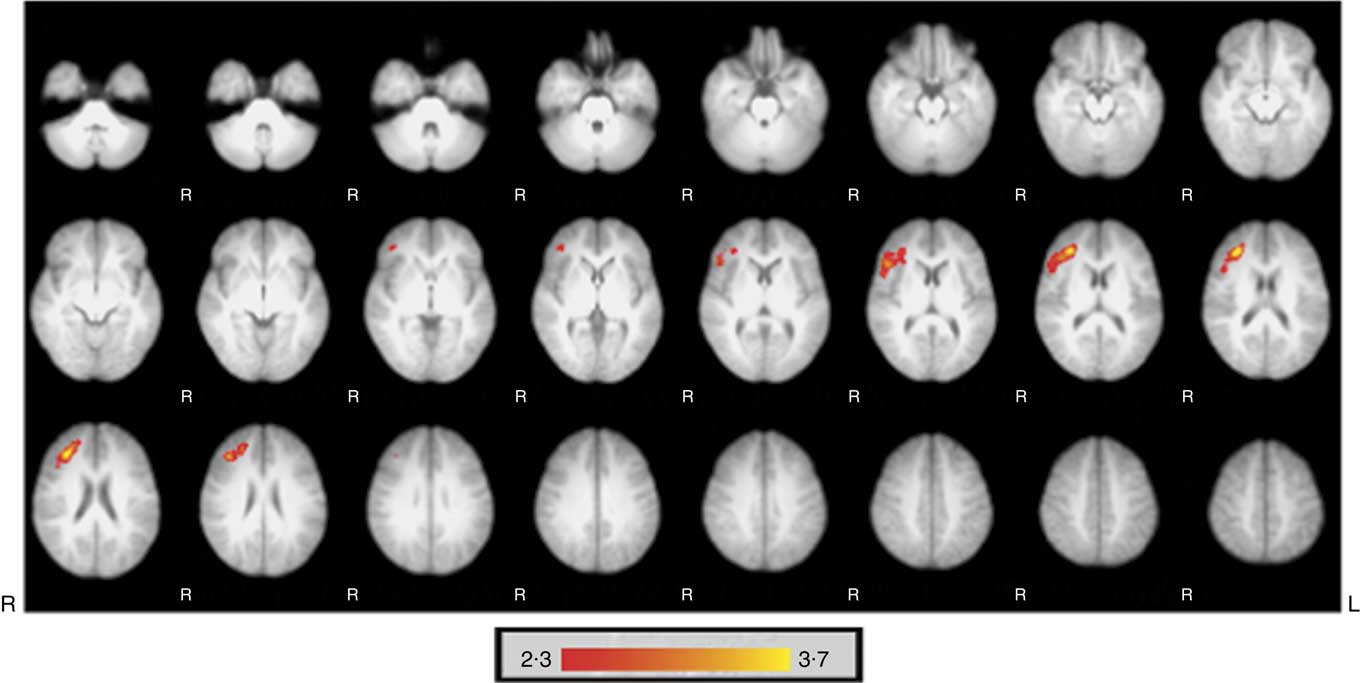

Fig. 1 shows significantly greater regional perfusion in the inferior frontal gyrus and middle frontal gyrus of the right hemisphere 2 h following consumption of the HF drink compared with the CT drink (988 voxels, coordinates: (X=37·9, Y=31·8, Z=17·8), statistics threshold: Z=3·69, P<0·001). There were no significant differences in regional perfusion between the HF and CT drinks 5 h after consumption, and no significant differences in global perfusion were observed between the two conditions at either time point.

Fig. 1 Significantly greater regional perfusion occurred in the inferior frontal gyrus and the medial frontal gyrus of the right hemisphere 2 h following the high-flavanone drink compared with the control drink. Activations are superimposed on axial slices of the Montreal Neurological Institute template brain and represent perfusion flow in ml/100 g tissue per min with ![]() indicating greater perfusion. The images were initially thresholded at Z>2·3 to identify activation clusters, and then a (corrected) cluster significance threshold of P<0·05 was applied.

indicating greater perfusion. The images were initially thresholded at Z>2·3 to identify activation clusters, and then a (corrected) cluster significance threshold of P<0·05 was applied.